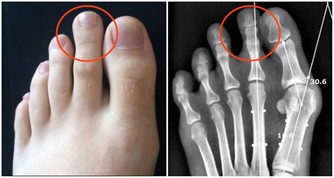

*****1.血管突起:*****

表層血管像蚯蚓一樣曲張,明顯凸出皮膚曲張呈團狀或結節狀。

這是最常見的靜脈曲張的症狀。